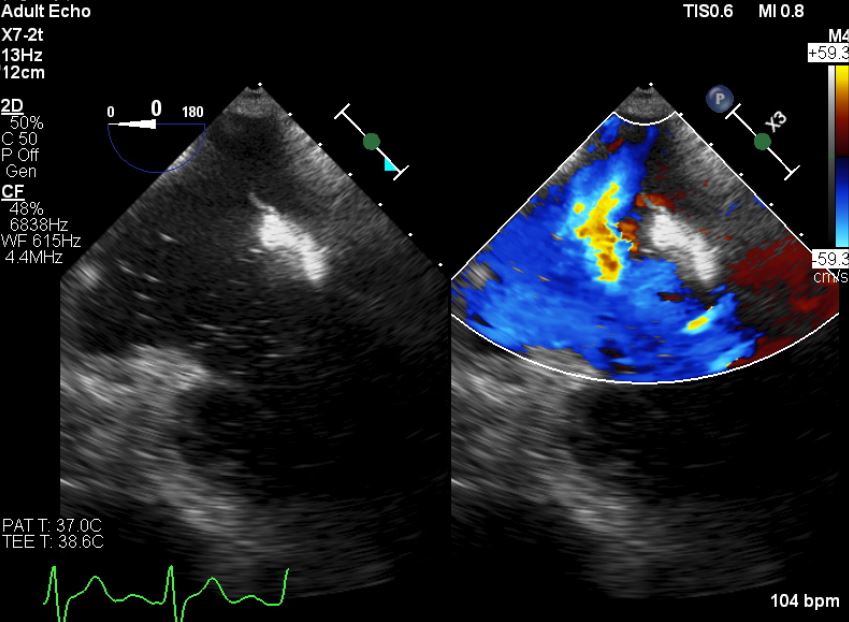

First, a trans-thoracic echocardiography(TTE) was done, there is a defect over the intra-atrial septum (IAS) with a dilated right heart. The doppler study exhibited a left to right shunting. A trans-oesophageal echocardiography (TOE) was done to assess the IAS & he has a secundum atrial septal defect(ASD), with anterior wall deficits but preserved inferoposterior wall length, largest diameter measuring 38.7mm. Estimated pulmonary arterial systolic pressure was 17 + 3 mmHG.

A right heart catheterisation was done, With Fick’s method revealing the pulmonary vascular resistance 2.83 wood unit indicating the need for ASD’s closure. A significant discrepancy arose in determining the true diameter of the ASD. In contrary to previous echocardiography, a repeated peri-procedural TTE measured it at 32mm with balloon inflation to occlude the defect. A decision was made to use a size 36mm occluder.